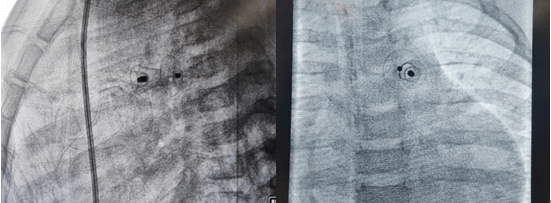

2021年11月12日,延安大学咸阳医院心血管病院吴栋梁院长、李阳主任介入团队为一例年仅13个月的女性患儿进行了先天性心脏病动脉导管未闭介入封堵手术。这是我院迄今为止介入封堵治疗年龄最小、体重最轻的患儿,手术过程顺利,封堵成功,解决了一家人的痛苦,患儿术后恢复良好,于2021年11月17日顺利出院。

先天性心脏病发病率已逐年下降,但因我国人群基数大,所以患者并不少见,先天性心脏病也是心血管疾病中为数不多的可通过介入或者外科手术得到根治的疾病之一,一般手术多建议在3岁以后进行,3岁以内患儿因体重太小,对患儿进行动静脉穿刺置管、手术操作过程及麻醉难度明显增加。该患儿体重仅10kg,身高仅70cm多一点,因动脉导管分流量较大,影响患儿发育,反复因肺部感染诱发心衰,并已经出现左房左室扩大,需尽早手术,否则出现心衰加重可能错过手术时机,但患儿家属对外科开胸心存畏惧,而且外科手术后胸部手术瘢痕明显影响女性患者的美观,通过多方打听,患儿联系到了何克强医生、李阳主任及吴栋梁院长手术团队,家属对医生期望值极高,因患儿情况特殊,吴栋梁院长及心血管内科五病区团队术前对患儿手术情况进行讨论,制定严密的手术方案,对手术中可能出现的难点进行充分的准备,最终在穿刺及麻醉成功后1小时内便顺利完成手术,此例手术的开展,标志着我院在先心病介入治疗方面再上新台阶,患儿术后恢复非常好,得到了患儿家属的肯定,解决了患儿一家的困扰。